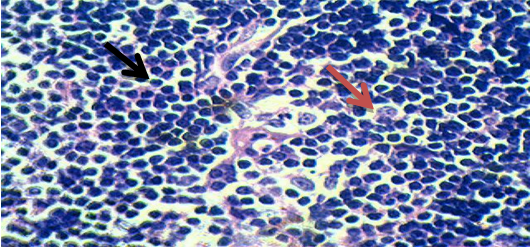

Fig. 1: Thymus section of group 1 (normal control), 40X

Section of thymus showed that the integrity of thymus was maintained in group–I. In fig. 1 black arrow indicates normal lymphocytes and the red arrow indicates concentrically arranged, swollen, and keratinized reticular cells that form Hassall's corpuscles.